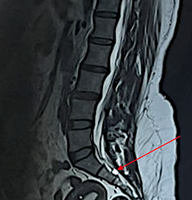

Case Report: We present three cases of hand enchondroma involving the phalanges in patients aged 20–37 years. Clinical features included fusiform swelling, pain, and, in one case, pathological fracture. Radiographs showed well-circumscribed lytic lesions with chondroid matrix. All cases were treated with intralesional curettage, cavity filling with cancellous autograft harvested from the olecranon, and prophylactic K-wire fixation. Histopathology confirmed enchondroma in each case. Postoperatively, patients underwent short-term immobilization followed by physiotherapy. At 12 weeks, all achieved full functional recovery with radiological consolidation and no recurrence or complications.

A 20-year-old female sustained trivial trauma to the left little finger, followed by acute pain, swelling, and deformity. Radiographs showed an enchondroma of the proximal phalanx complicated by a pathological fracture with cortical breach. A similar dorsal approach was employed; after curettage and grafting with olecranon cancellous bone, prophylactic K-wire fixation was used to stabilize the fracture site. Histopathology demonstrated mature cartilage with uniform chondrocytes, confirming enchondroma without evidence of malignancy. Sutures were removed at 2 weeks, and K-wires at 6 weeks, followed by physiotherapy. By 12 weeks, radiographs showed satisfactory union with graft consolidation. The patient achieved complete functional recovery, including grip and pinch strength, and resumed regular household activities without restriction.

Sutures were removed at 2 weeks. Physiotherapy was initiated after K-wire removal to prevent stiffness. Radiographs at 6 and 12 weeks demonstrated consolidation of grafts and obliteration of cavities (Fig. 3). All patients regained full range of motion and resumed normal activities without recurrence or complications.